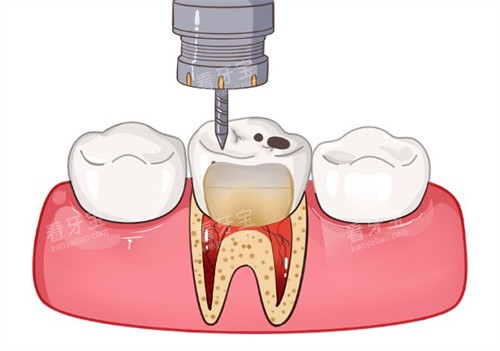

设备方面,诺贝尔口腔投入超2000万元引进了一批高端设备,像德国西诺德3D口腔CT、美国NEWTOM口腔CT、显微根管治疗仪等,这些设备能帮助医生更比较准地定位根管,让治疗过程更精细,减少对牙齿的损伤。而且他们采用不痛根管治疗技术,治疗时几乎没什么痛感,深入打破了“根管治疗很疼”的固有印象。